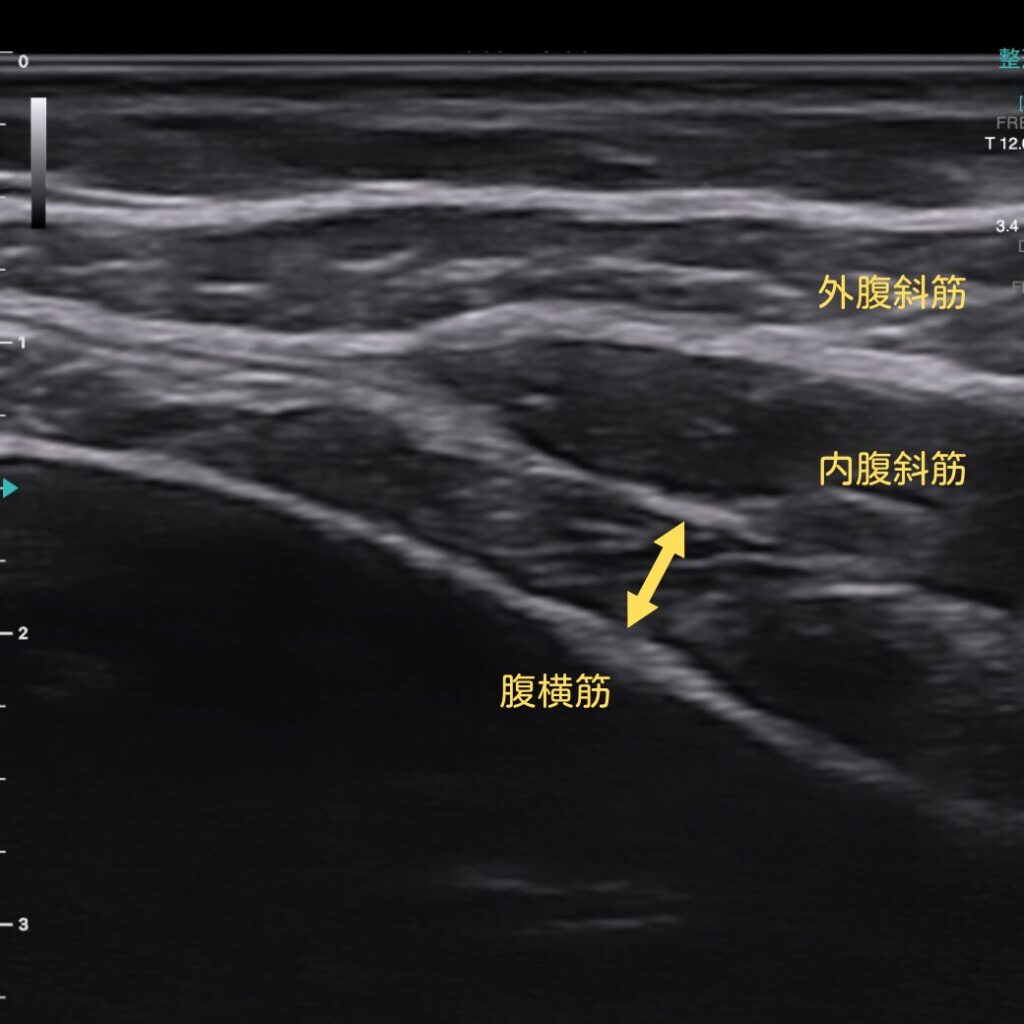

さらに、腹横筋(インナーマッスル)が実際に使えているか

超音波エコーでリアルタイムに“見える化”しながら確認できます。

「効いているつもり」を避け、確実に正しいトレーニング効果へつなげます。

エコーで確認すると、体幹が働いた瞬間がその場で見えます!